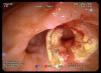

Mujer de 87 años que ingresa en el servicio de cirugía por ictericia, colangitis y pancreatitis aguda. Se instauró tratamiento con sueroterapia y antibióticos, que consiguió la estabilización hemodinámica de la paciente. En una colangiopancreatografía por resonancia magnética (fig. 1) se observó un defecto de repleción en el colédoco distal. Con la intención de desobstruir la vía biliar, se realizó una colangiopancreatografía retrógrada endoscópica (CPRE), empleando sedación consciente con midazolam y dolantina. En la endoscopia, la ampolla de Vater se encontró muy abultada, con un orificio en el que parecía entreverse una coledocolitiasis (fig. 2). Se realizó una esfinterotomía biliar amplia (fig. 3) y se extrajo una coledocolitiasis de 13 mm de diámetro máximo, que estaba impactada en la ampolla (fig. 4). La evolución de la paciente fue satisfactoria.

Fig. 4